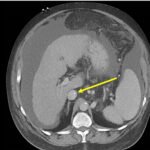

Endovascular coil embolization continues to become a more frequent modality of addressing hemorrhage and bleeding in patients. Migration refers to the coil unraveling or moving from the original embolization site. Migration of a coil is a known complication which can lead to serious consequences based on where the coil migrates. Despite increasing efforts to improve safety and technique, the risk of migration remains. We present a case of an embolization coil that migrated to the right ventricle, which was incidentally found roughly 2 months after undergoing an interventional radiology procedure for gastric variceal bleeding. The patient presented to the emergency department with dyspnea and abdominal pain. Unique images were obtained during his visit and in subsequent follow-up. As use of vascular embolization coils continues to become more commonplace, understanding the risks and complications of these procedures remains an important aspect of providing care for patients once they have left the interventional radiology suite. Coil migration should be a differential to consider in patients who present to the emergency department with signs or symptoms of arrhythmia or pulmonary embolism who have undergone a coil embolization procedure.